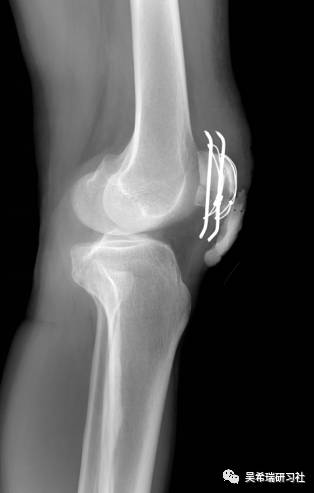

髌骨手术后继发感染40天髌韧带外露

TIPS:清创后再固定伤口用抗生素骨水泥感染得到控制后皮肤牵张闭合伤口2个月内手法松解关节,骨牵引维持5天